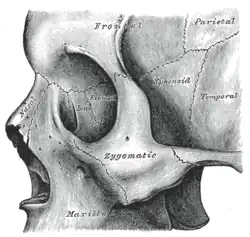

Articulação

O osso esfenoide articula-se com os ossos:[3]

- Frontal

- Parietal

- Temporal

- Occipital

- Zigomático

- Vômer

- Etmoide

- Palatino

Visto de lado